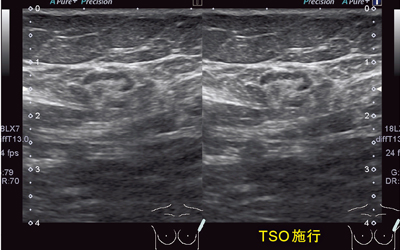

図5は,乳腺腫瘤の症例画像である。TSOを施行することで,方位分解能が向上し,腫瘤の輪郭や乳腺内部の構造がシャープに描出される。図6は,腋窩リンパ節腫脹の症例であるが,TSO施行により辺縁や内部の構造が明瞭に描出されるようになっている。高周波リニアにはAuto TSO機能が搭載されており,ボタン1つでTSO施行が可能である。

図5 乳腺腫瘤症例でのTSO施行例 脂肪組織の厚い乳房や腋窩などで有効である。

図5 乳腺腫瘤症例でのTSO施行例

脂肪組織の厚い乳房や腋窩などで有効である。

図6 腋窩リンパ節腫脹の症例 高周波リニアプローブにはAuto TSOが搭載されている。

図6 腋窩リンパ節腫脹の症例

高周波リニアプローブにはAuto TSOが搭載されている。